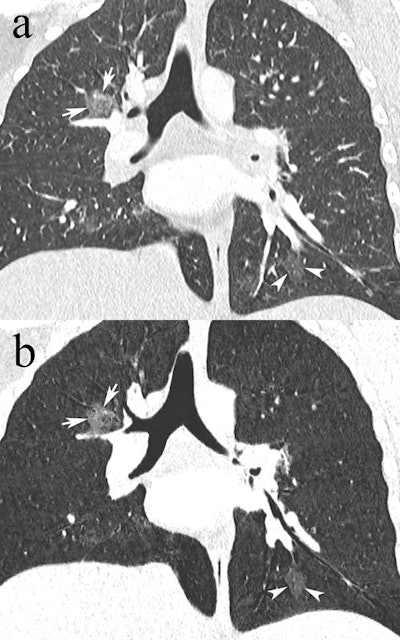

Coronal reformatted CTPA in a 23-year-old pregnant woman presenting with dyspnea and desaturation. Images in lung window (a) showed multifocal pulmonary ground-glass opacities in the right upper lobe (white arrows) and left lower lobe (white arrowheads), better depicted on minimum-intensity projection (b), consistent with viral pneumonia. The nasal swab was positive for influenza type A. Image courtesy of Drs. David Rotzinger and Sabine Schmidt."Our paper indicates that despite the low PE rate, CTPA is still a useful test when clinical or biological features suggest PE in pregnant women, because alternative diagnoses are frequently uncovered and influence clinical decision-making," Rotzinger and one of his co-authors, emergency radiology consultant Dr. Sabine Schmidt, told AuntMinnieEurope.com.